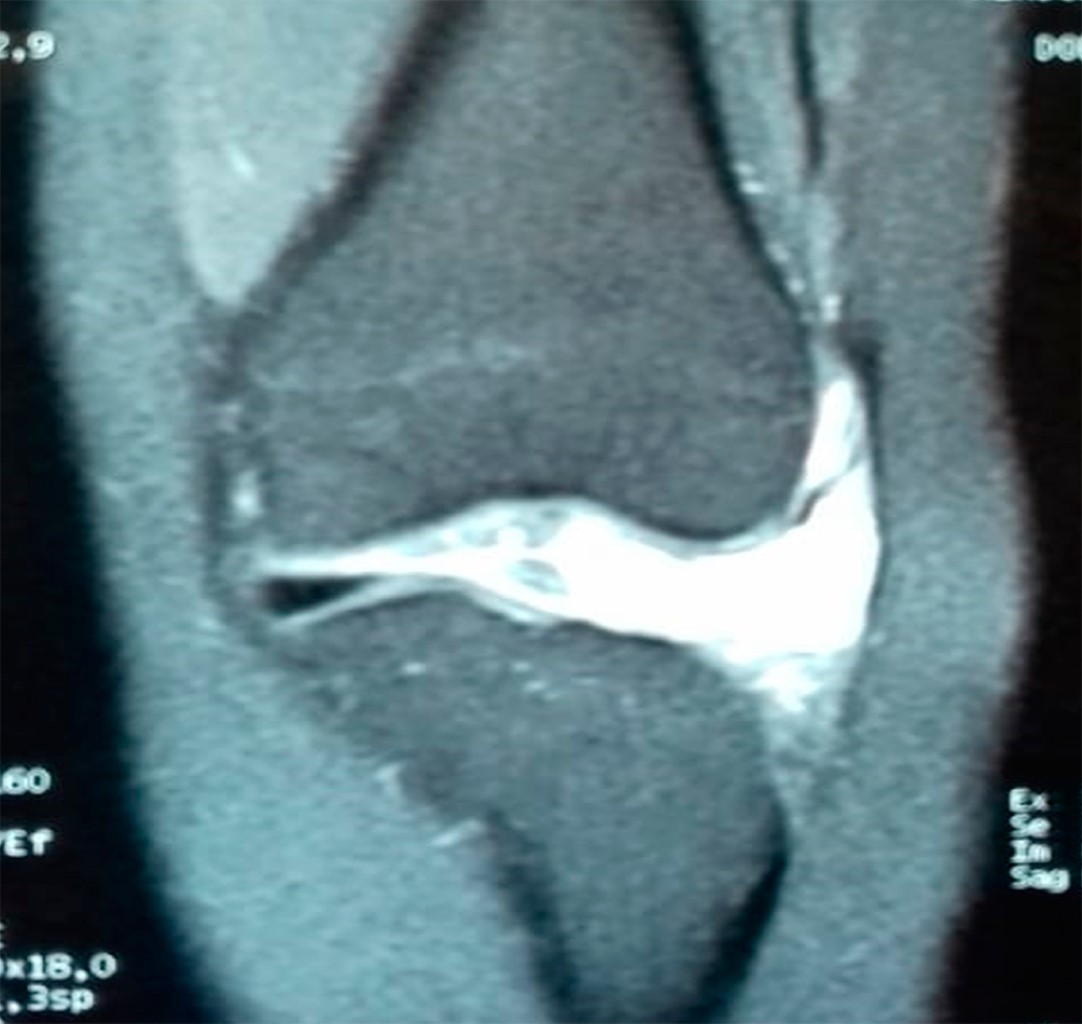

En la exploración física se observa una marcha plantígrada no claudicante independiente tolerando talo equino, rodilla izquierda sin presencia de edema, dolor en línea articular de predominio lateral, el cual se intensifica a la palpación, cajón anterior y posterior negativo, pruebas meniscales McMurray y Appley negativos, Langman negativo, se aplica cuestionario KOOS (Knee Injury and Osteoarthritis Outcome Score), el cual arroja un resultado con limitación funcional impidiendo actividades de la vida diaria, dolor EVA 8/10. Se procede a realizar estudios de imagen: proyecciones radiográficas anteroposterior y lateral de rodilla sin lesiones óseas ni datos de importancia a nivel articular; por antecedente de bloqueo de rodilla se solicita resonancia magnética de miembro izquierdo en la cual se reporta meniscopatía medial grado I a nivel de cuerno posterior, fractura horizontal de cuerno anterior de menisco lateral con formación asociada de gran quiste parameniscal con ejes mayores de 2.7 × 3.7 cm, el resto sin alteraciones (Figuras 1 y 2).

Conviene distinguir entre quistes parameniscales e intrameniscales. La resonancia magnética permite visualizar quistes meniscales en los cortes coronales, sagitales y axiales. Sin embargo, los cortes coronales son los que mejor muestran los quistes, la lesión meniscal y la lesión horizontal comunicante.

La RM se convierte así en el método de estudio de elección cuando se evalúa un posible quiste meniscal, porque informa su localización y tamaño de la lesión meniscal, así como también la existencia de patología asociada extra- e intraarticular.11

Figura 1